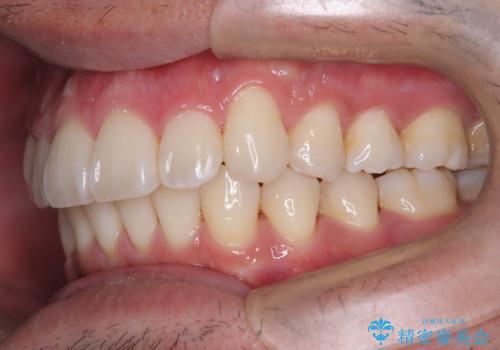

【インビザライン】前歯の凸凹を解消。

- 前歯の凸凹を主訴に来院されました。

もともと、顎が左にシフトしていたので正中が合わないことを説明した後、矯正を開始しています。

短期間で前歯のがたがたがきれいになり、満足していただけました。